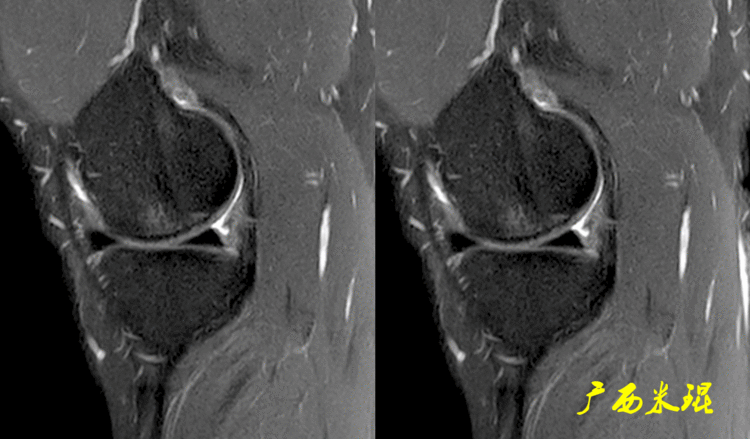

(1)假桶柄MR冠状位上偏后的层面,“C”形或“O”形的内外侧半月板偏后侧层面有可能同时扫描到半月板体部和后角,容易误诊为桶柄状撕裂,而矢状位或横断位上半月板形态是正常的。

下面这张MR冠状位显示为内侧半月板后角的假桶柄,其母体(图片中内侧的那一部分半月板)并没有变小、形态及信号均正常。

下面这张MR冠状位显示为外侧半月板后角的假桶柄,尽管在髁间窝发现半月板信号,但其母体(图片中外侧的那一部分半月板)并没有变小、形态及信号均正常。